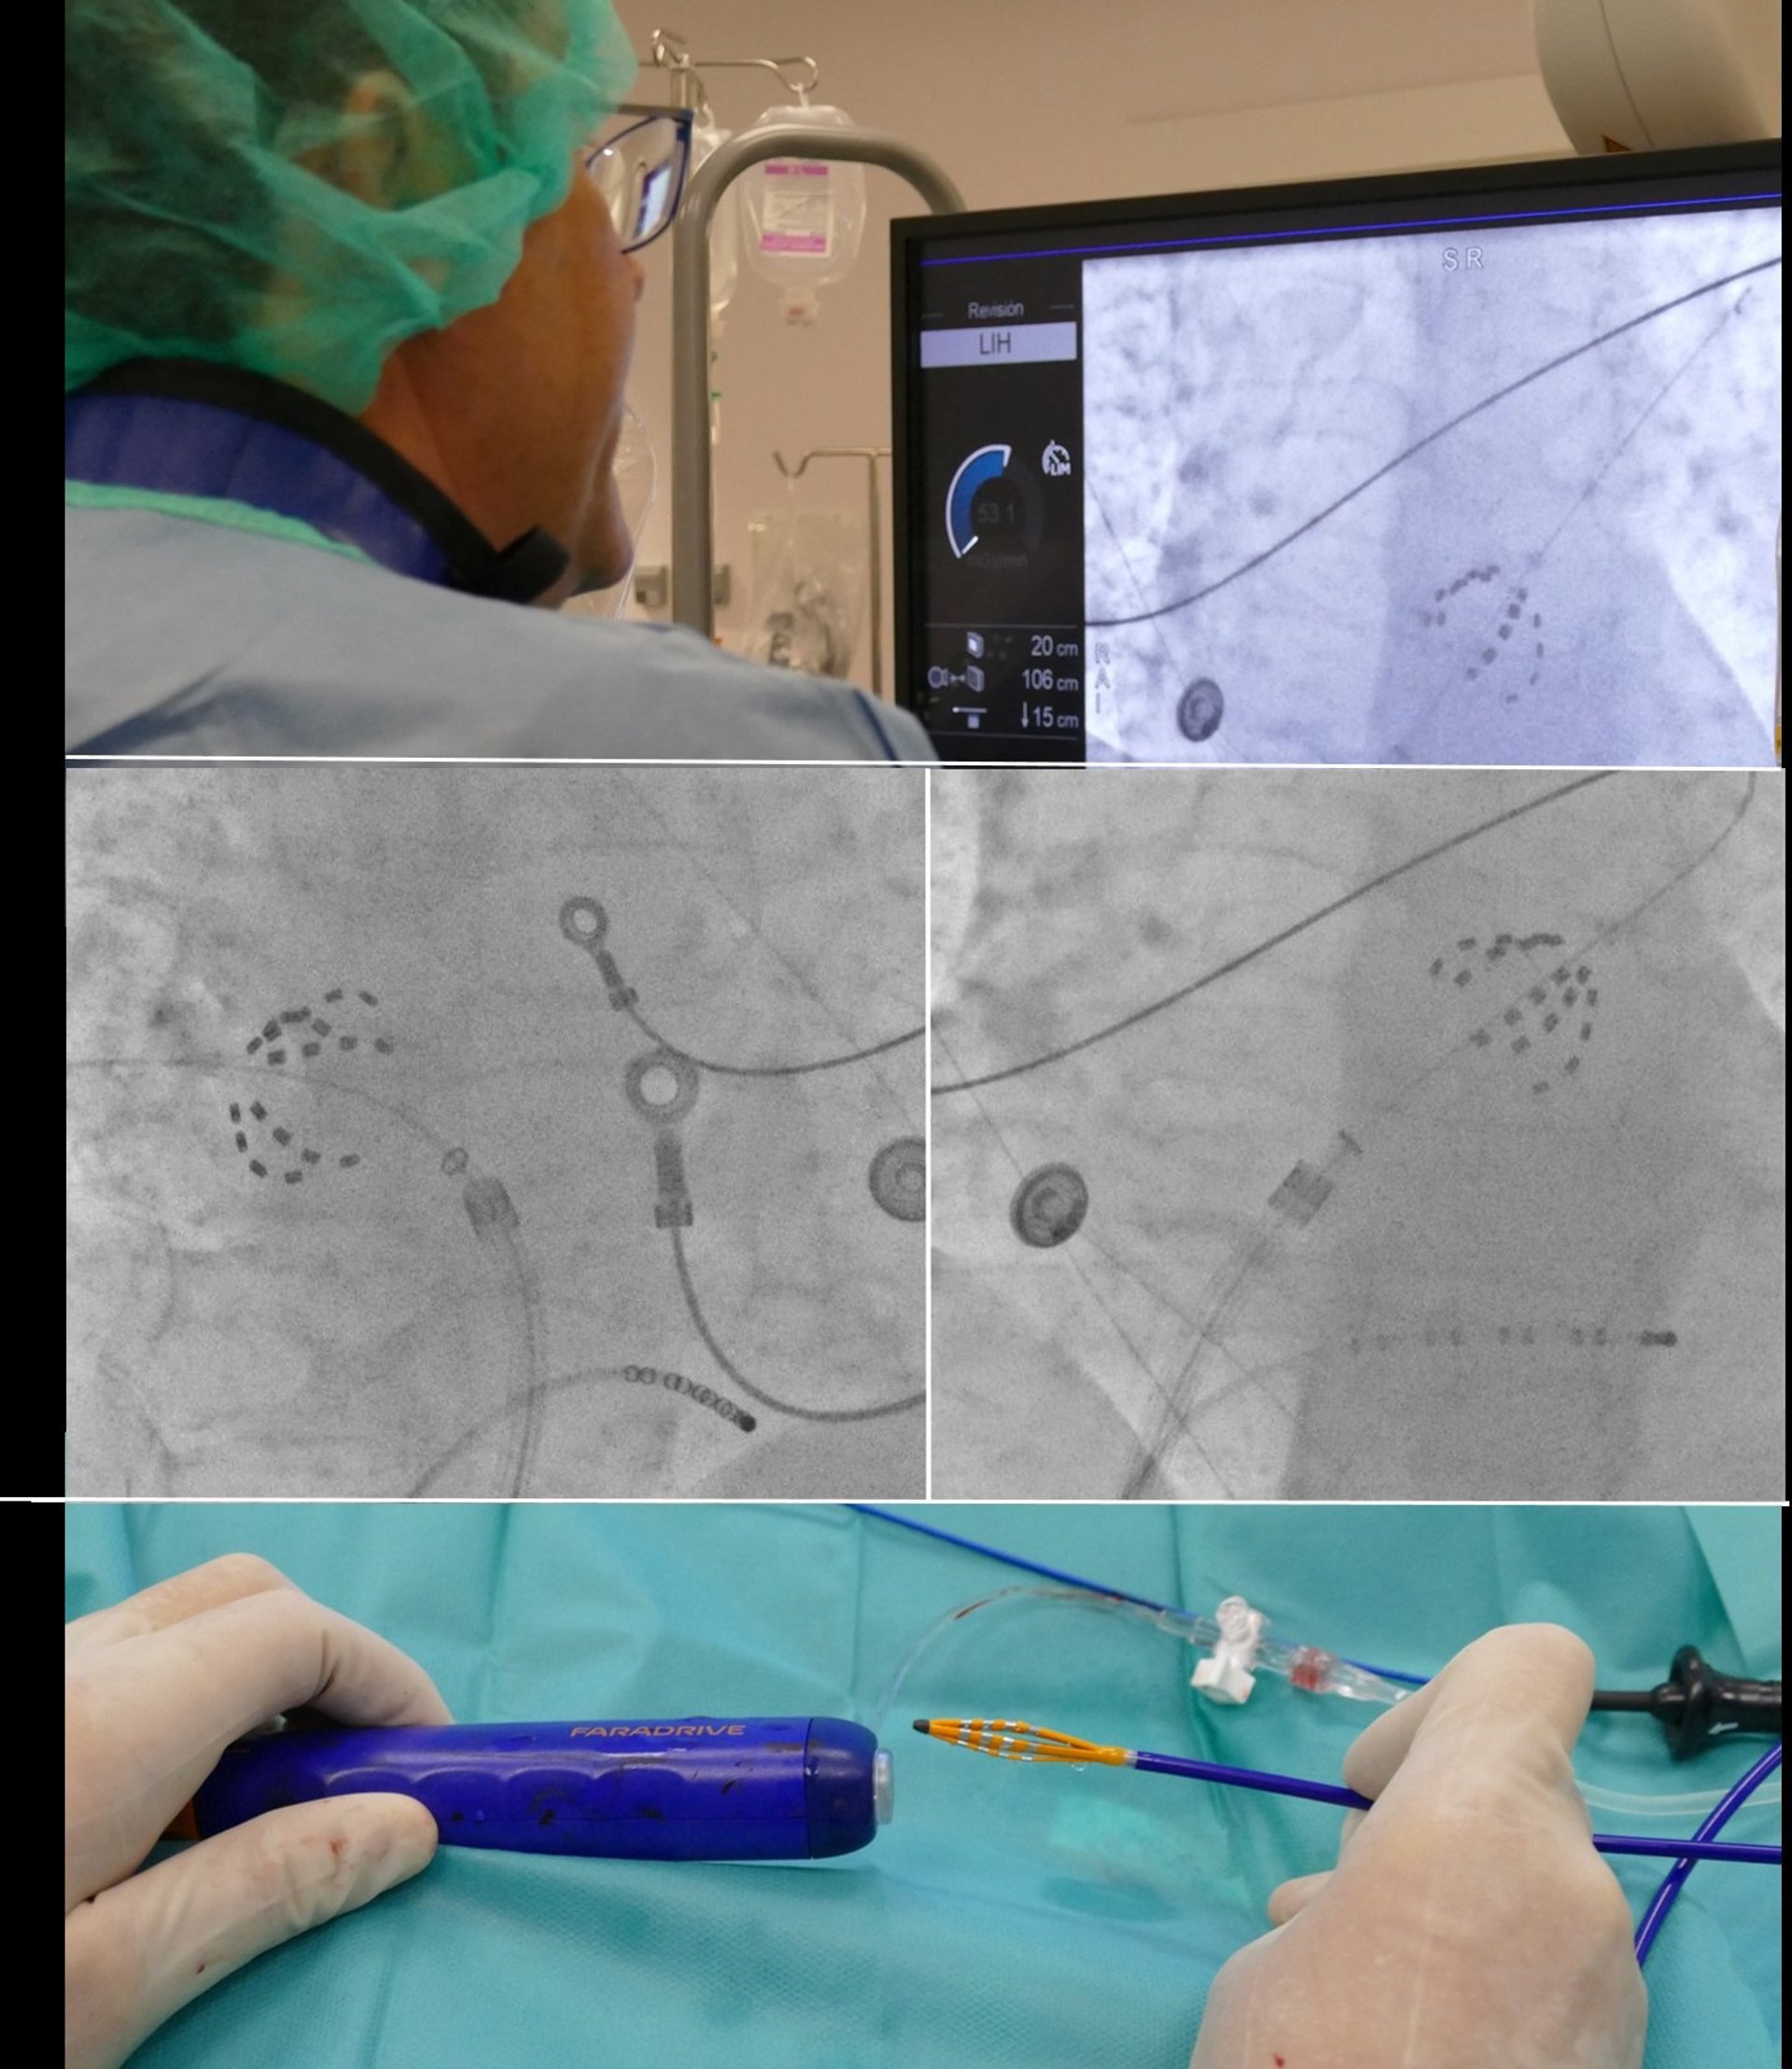

Imágenes del procedimiento de ablación realizado mediante técnica de electroporación

Imágenes del procedimiento de ablación realizado mediante técnica de electroporación - HOSPITAL UNIVERSITARIO RUBER JUAN BRAVO

Por ello, la incorporación de la ablación por electroporación tiene varias ventajas. Esta técnica consiste en la emisión, a través de un catéter, de campos eléctricos que destruyen selectivamente las células cardiacas que propagan la fibrilación auricular, respetando el resto de tejidos. "El efecto observado de la electroporación en la actividad eléctrica cardiaca es inmediato, lo que permite realizar la intervención en menos tiempo y de una forma, incluso, más segura", ha resaltado Fontenla.